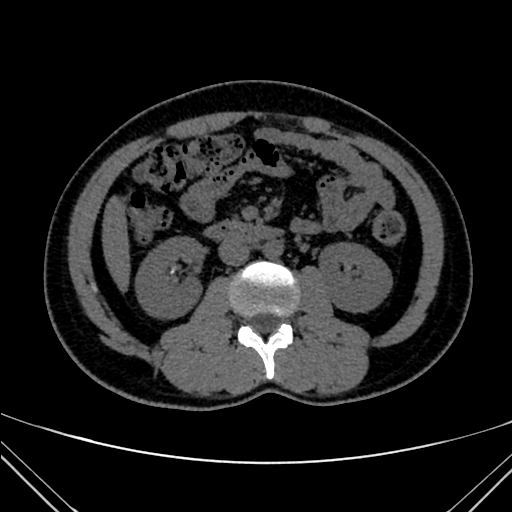

img

Cyst